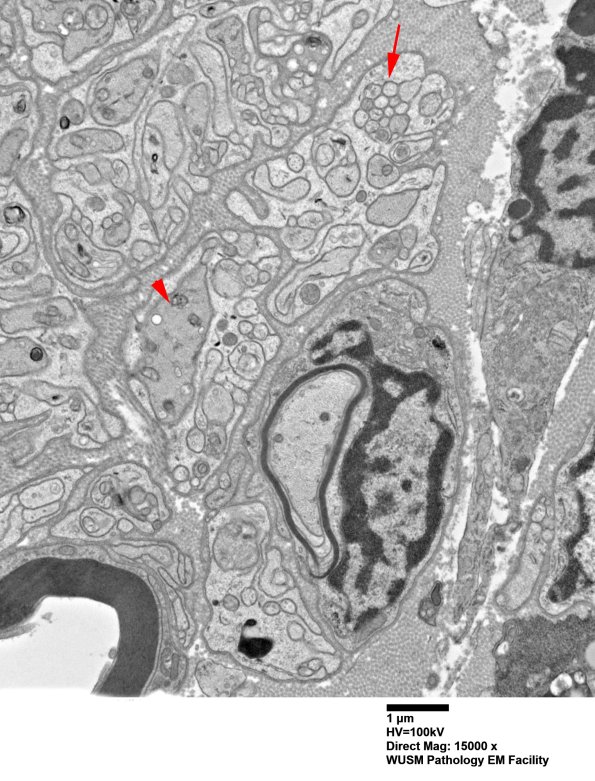

A thinly myelinated axon is adjacent to a pre-myelinated axon (arrowhead) of approximately the same size. There are collections of small axons (arrow) which lie together in a trough of Schwann cell processes. (electron micrograph)